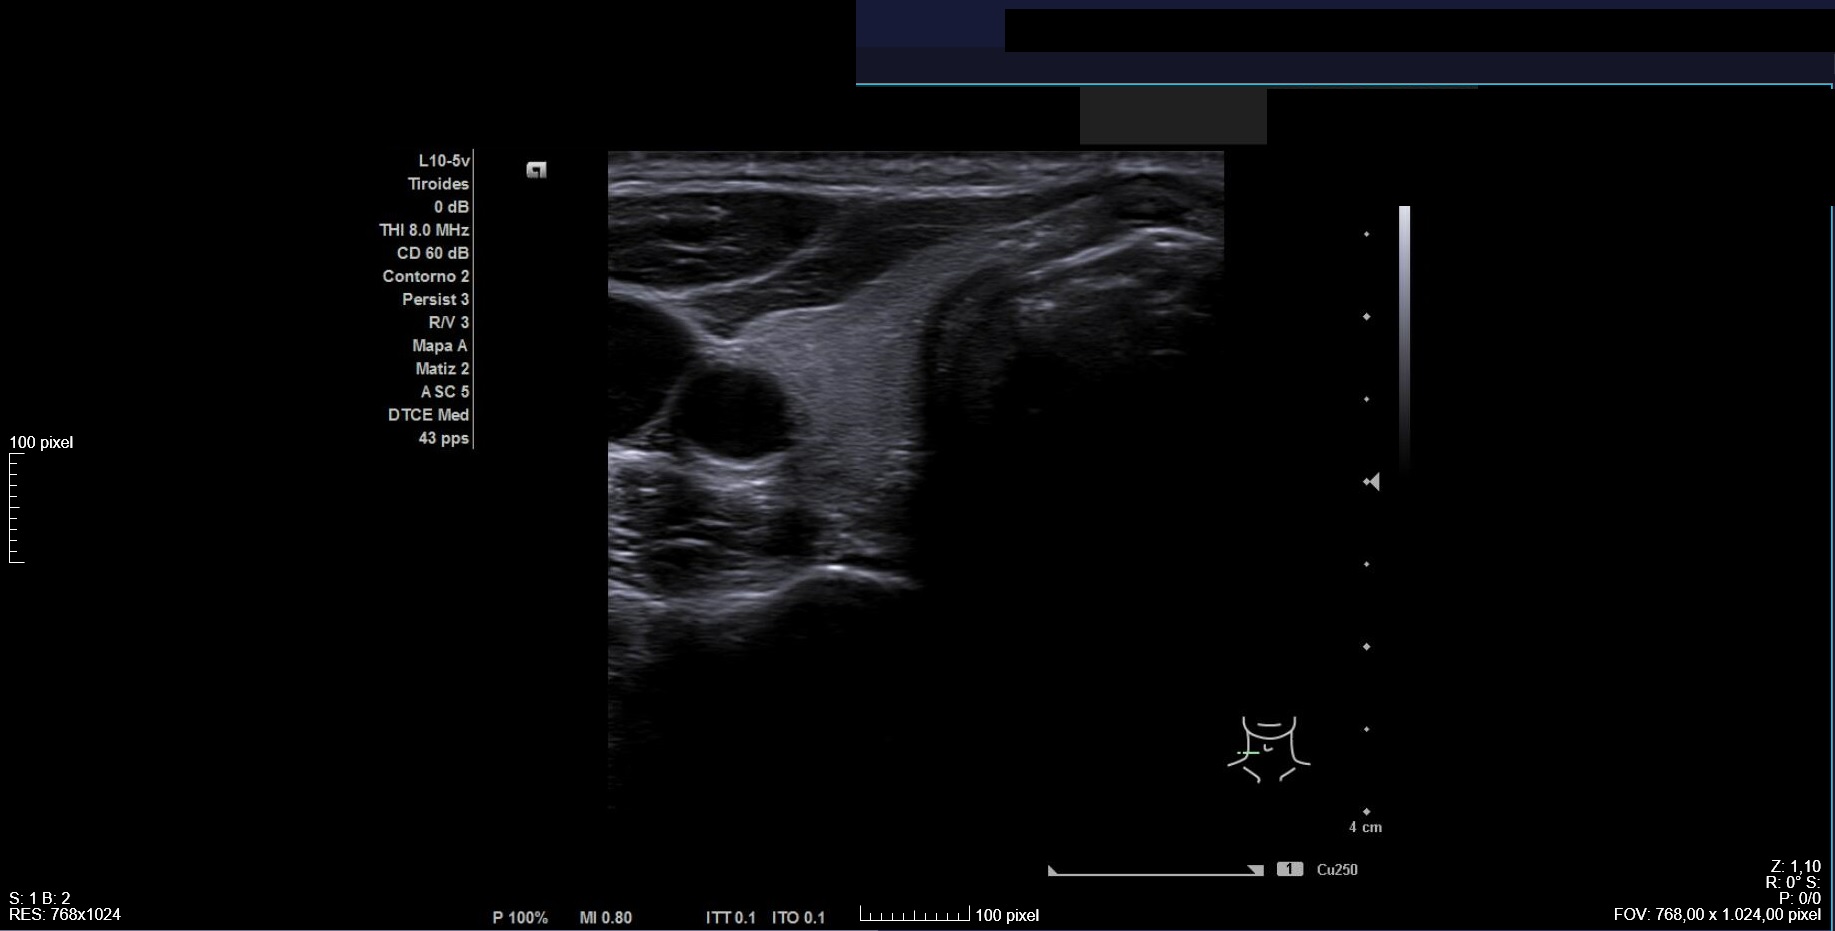

Ecografía clínica: tiroides de tamaño normal con ecoestructura homogénea. En lóbulo tiroideo izquierdo nódulo de 3 cm, anecoico, márgenes bien definidos con imagen hiperecoica en su interior (Imágenes 1, 2 y 3).

Ante clínica y ecografía compatible con hemorragia en nódulo tranquilizamos a la paciente, informándole sobre pronóstico y actitud a seguir. Citamos para seguimiento clínico en 3 semanas, con desaparición del dolor y disminución de tamaño del nódulo.